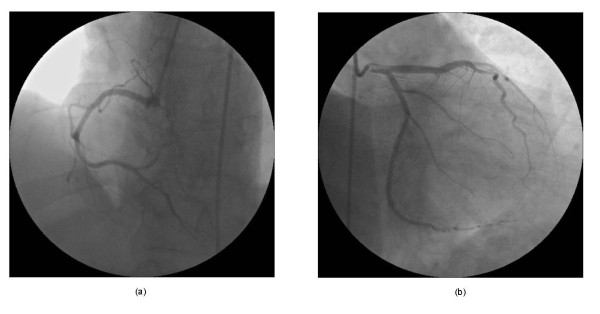

医院的CT与核磁共振影像中都看不出这位吃辣椒的小哥有什么大问题,也没有因此造成语言障碍或视力问题,但医生仔细检查他的大脑血管后,结果大为吃惊。吃下辣椒后,小哥大脑中的许多动脉血管严重收缩,造成了可逆性脑血管收缩综合征(RCVS),也就解释了为什么他会产生严重的头痛症状。数周的跟踪诊断后,医生发现,他的脑血管在五周后渐渐恢复正常。但是,医生提醒,这种脑血管收缩症可能会引起中风。